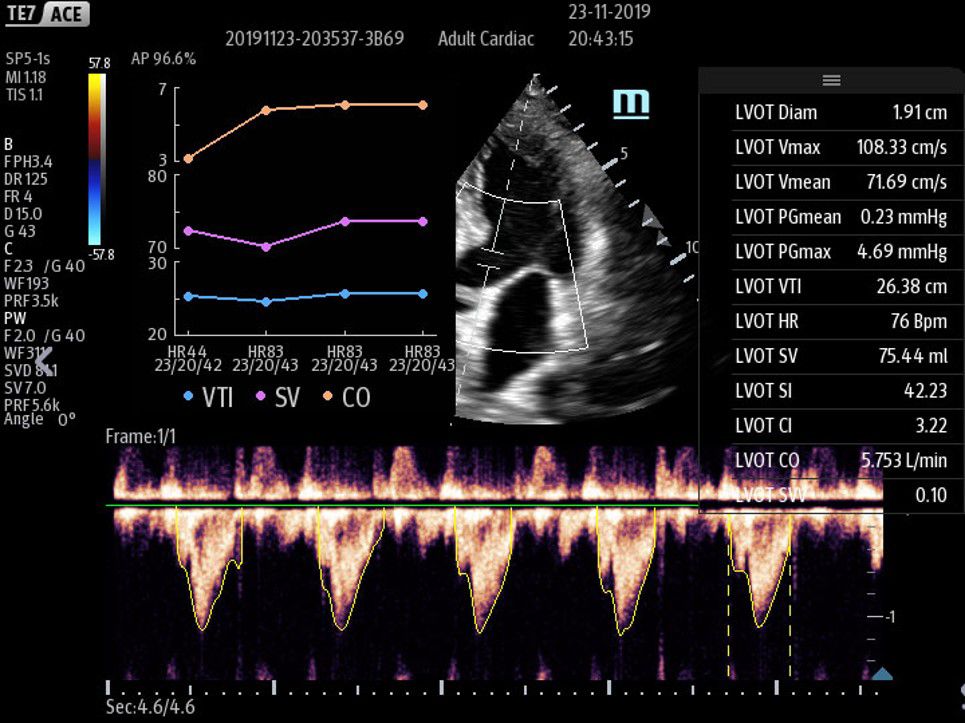

Picture3

• Picture3